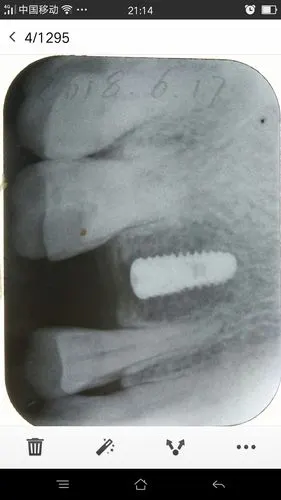

吴女士种植带冠后的牙片显示,种植体就位精准,受力均衡